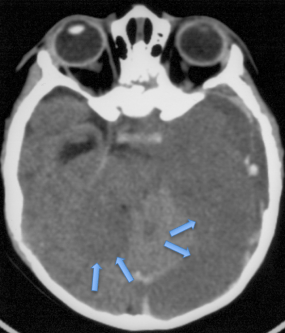

l’engagement rétro-mésencéphalique

c’est une figure particulière de dysfonctionnement de valve qui provoque la descente trans-tentorielle des hémisphères cérébraux sous pression en arrière du mésencéphale ; ceci donne une imagerie parfois déroutante (Cf. ci-dessous), mais qui traduit une HTIC sévère.